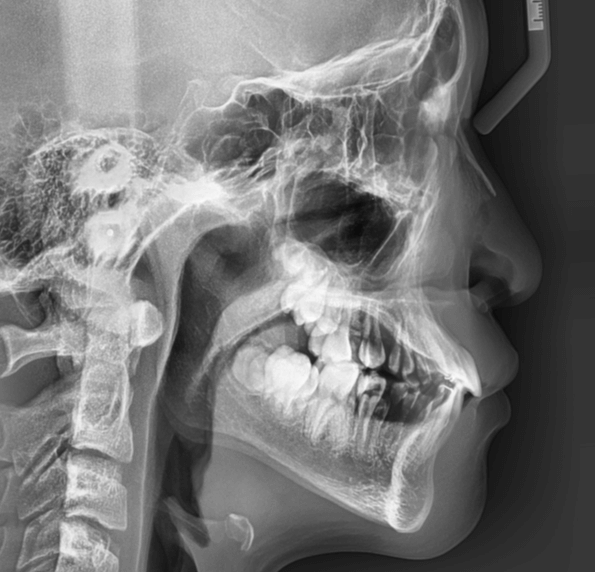

| 年齢・性別 | 11歳1ヶ月の女性 |

|---|---|

| 主訴 | 口元の突出感と歯並びが気になり、将来的な咬合状態を整える目的で来院された患者様です。 |

| 治療期間・回数 | 2年6ヶ月・25回 |

| 費用 | 720,000円 |